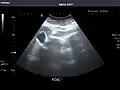

Spleen -

Spleen: Normal in size.